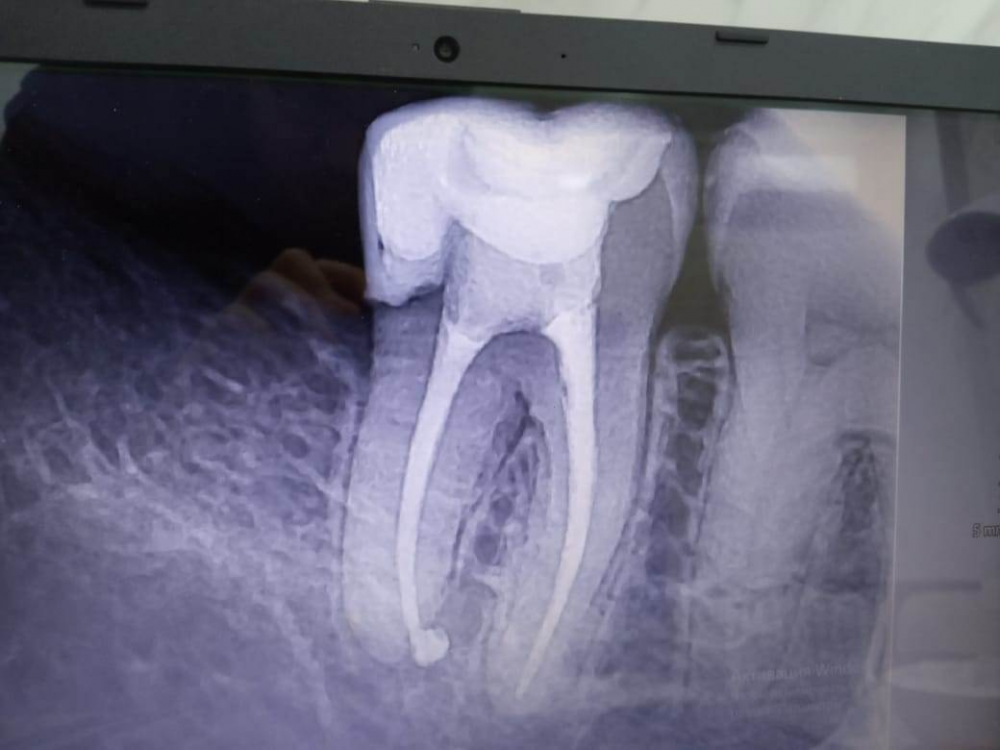

Aleksandr21321 Опубликовано 16 января, 2024 Поделиться Опубликовано 16 января, 2024 Вот снимки, но врач сказал, что снимкам не стоит на 100% доверять. Болит зуб или даже зубы при употреблении пищи, а также присутствует временами постоянное нытье зуба / зубов. Что делать, я и врачи (ходил к нескольким) совершенно не понимаем. Дело в том, что определить кто именно виновник, трудновато. В одном из зубов удален нерв, и при надавливании чувствуется, что ему некомфортно. Но не факт, что виновник проблем именно он... В интернете упомянул кто-то компьютерную томографию, которая стоит недешево. Скажите, стоит ли ее делать и как она поможет? Ссылка на комментарий

АнтонТЛТ Опубликовано 16 января, 2024 Поделиться Опубликовано 16 января, 2024 В нижнем 7 зубе щель между пломбой и зубом в районе корня под десной. Ссылка на комментарий

Aleksandr21321 Опубликовано 16 января, 2024 Автор Поделиться Опубликовано 16 января, 2024 (изменено) 47 минут назад, АнтонТЛТ сказал: В нижнем 7 зубе щель между пломбой и зубом в районе корня под десной. Из за этой щели может болеть при жевании? КТ стоит делать, чтобы подтвердить щель, а также узнать, может где нерв близок к пломбе? Или последнее и снимки показывают? Изменено 16 января, 2024 пользователем Aleksandr21321 Ссылка на комментарий

andraks Опубликовано 17 января, 2024 Поделиться Опубликовано 17 января, 2024 А не перелом ли это? Из за этого могла появиться щель под пломбой. Ссылка на комментарий